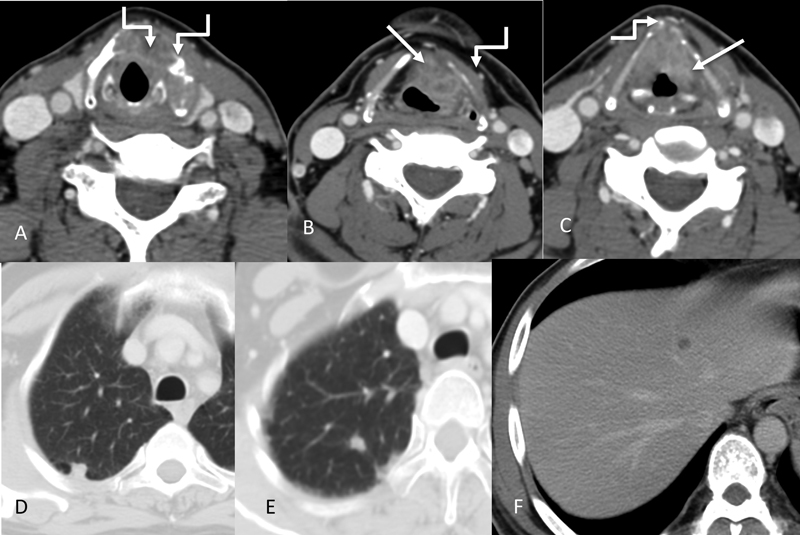

| Figure 9:Transglottic laryngeal cancer. Axial CT images (A–C) showing the primary enhancing mass (straight arrows) involving the true vocal cords bilaterally and left false cord. There is gross involvement of the thyroid cartilage (more on the left side) with subtle extralaryngeal spread anteriorly (shouldered arrows). Right arytenoid cartilage appears sclerosed. The left para glottic space is also involved. In addition, lung nodules and liver lesions were also identified (D–F).